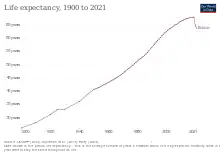

Under-5 mortality in 2019 was 26, half of what it was in 2006.[15] Infant mortality was 21.2 in 2019, approximately half of what it was in 2006.[16] Bolivia's maternal mortality rate is 160 per 100,000 which makes it one of the highest in the region and it is estimated to be even higher.[17] Before Evo Morales took office nearly half of all infants were not vaccinated and now nearly all are.[18]